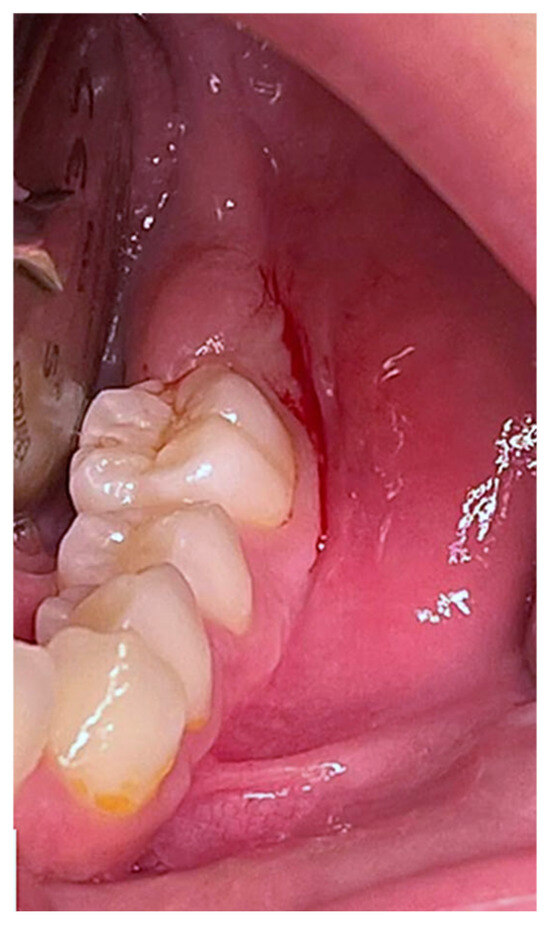

2.1. Case Presentation